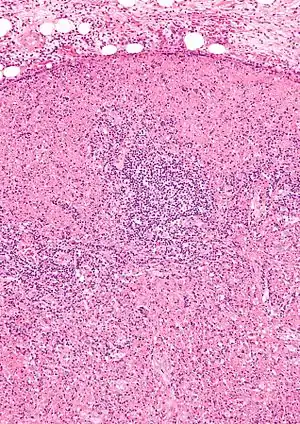

| Micrograph of a lymph node with Kikuchi disease showing the characteristic features (abundant histiocytes, necrosis without neutrophils). H&E stain. | |